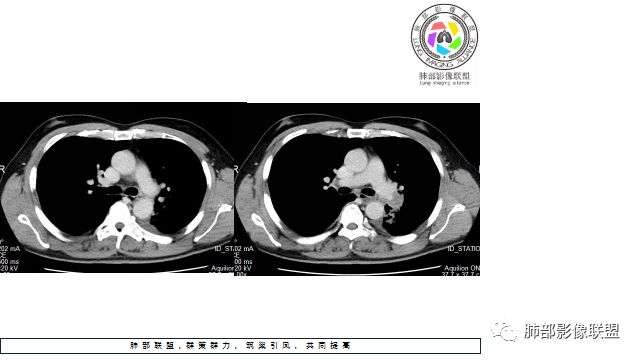

1.左下肺门区巨大肿块,支气管显示不清,轻度阻塞性炎症,没有明显肺不张,提示管腔受压狭窄可能性大于堵塞,这较少见于鳞癌。

3.病灶内密度均匀,轻到中度均匀强化,大病灶未见明显液化坏死区及空洞,不符合鳞癌而符合小细胞肺癌特点。

4.病灶内有肺动脉走形,血管局部受压,未见破坏,病灶乏血供,呈血管包埋或血管造影征;侵袭性力强及破坏力弱、血管漂浮都符合SCLC,所以鳞癌的可能性也不大。

5.左肺门块影或淋巴结肿大,竭力挤兑肺门血管结构,呈冰冻肺门;有时候SCLC可以单独呈现冰冻肺门,而没有没有冰冻纵隔。

7.须特别注意的是,肺门区的融合块影,不排除它可能仅仅为转移淋巴结。